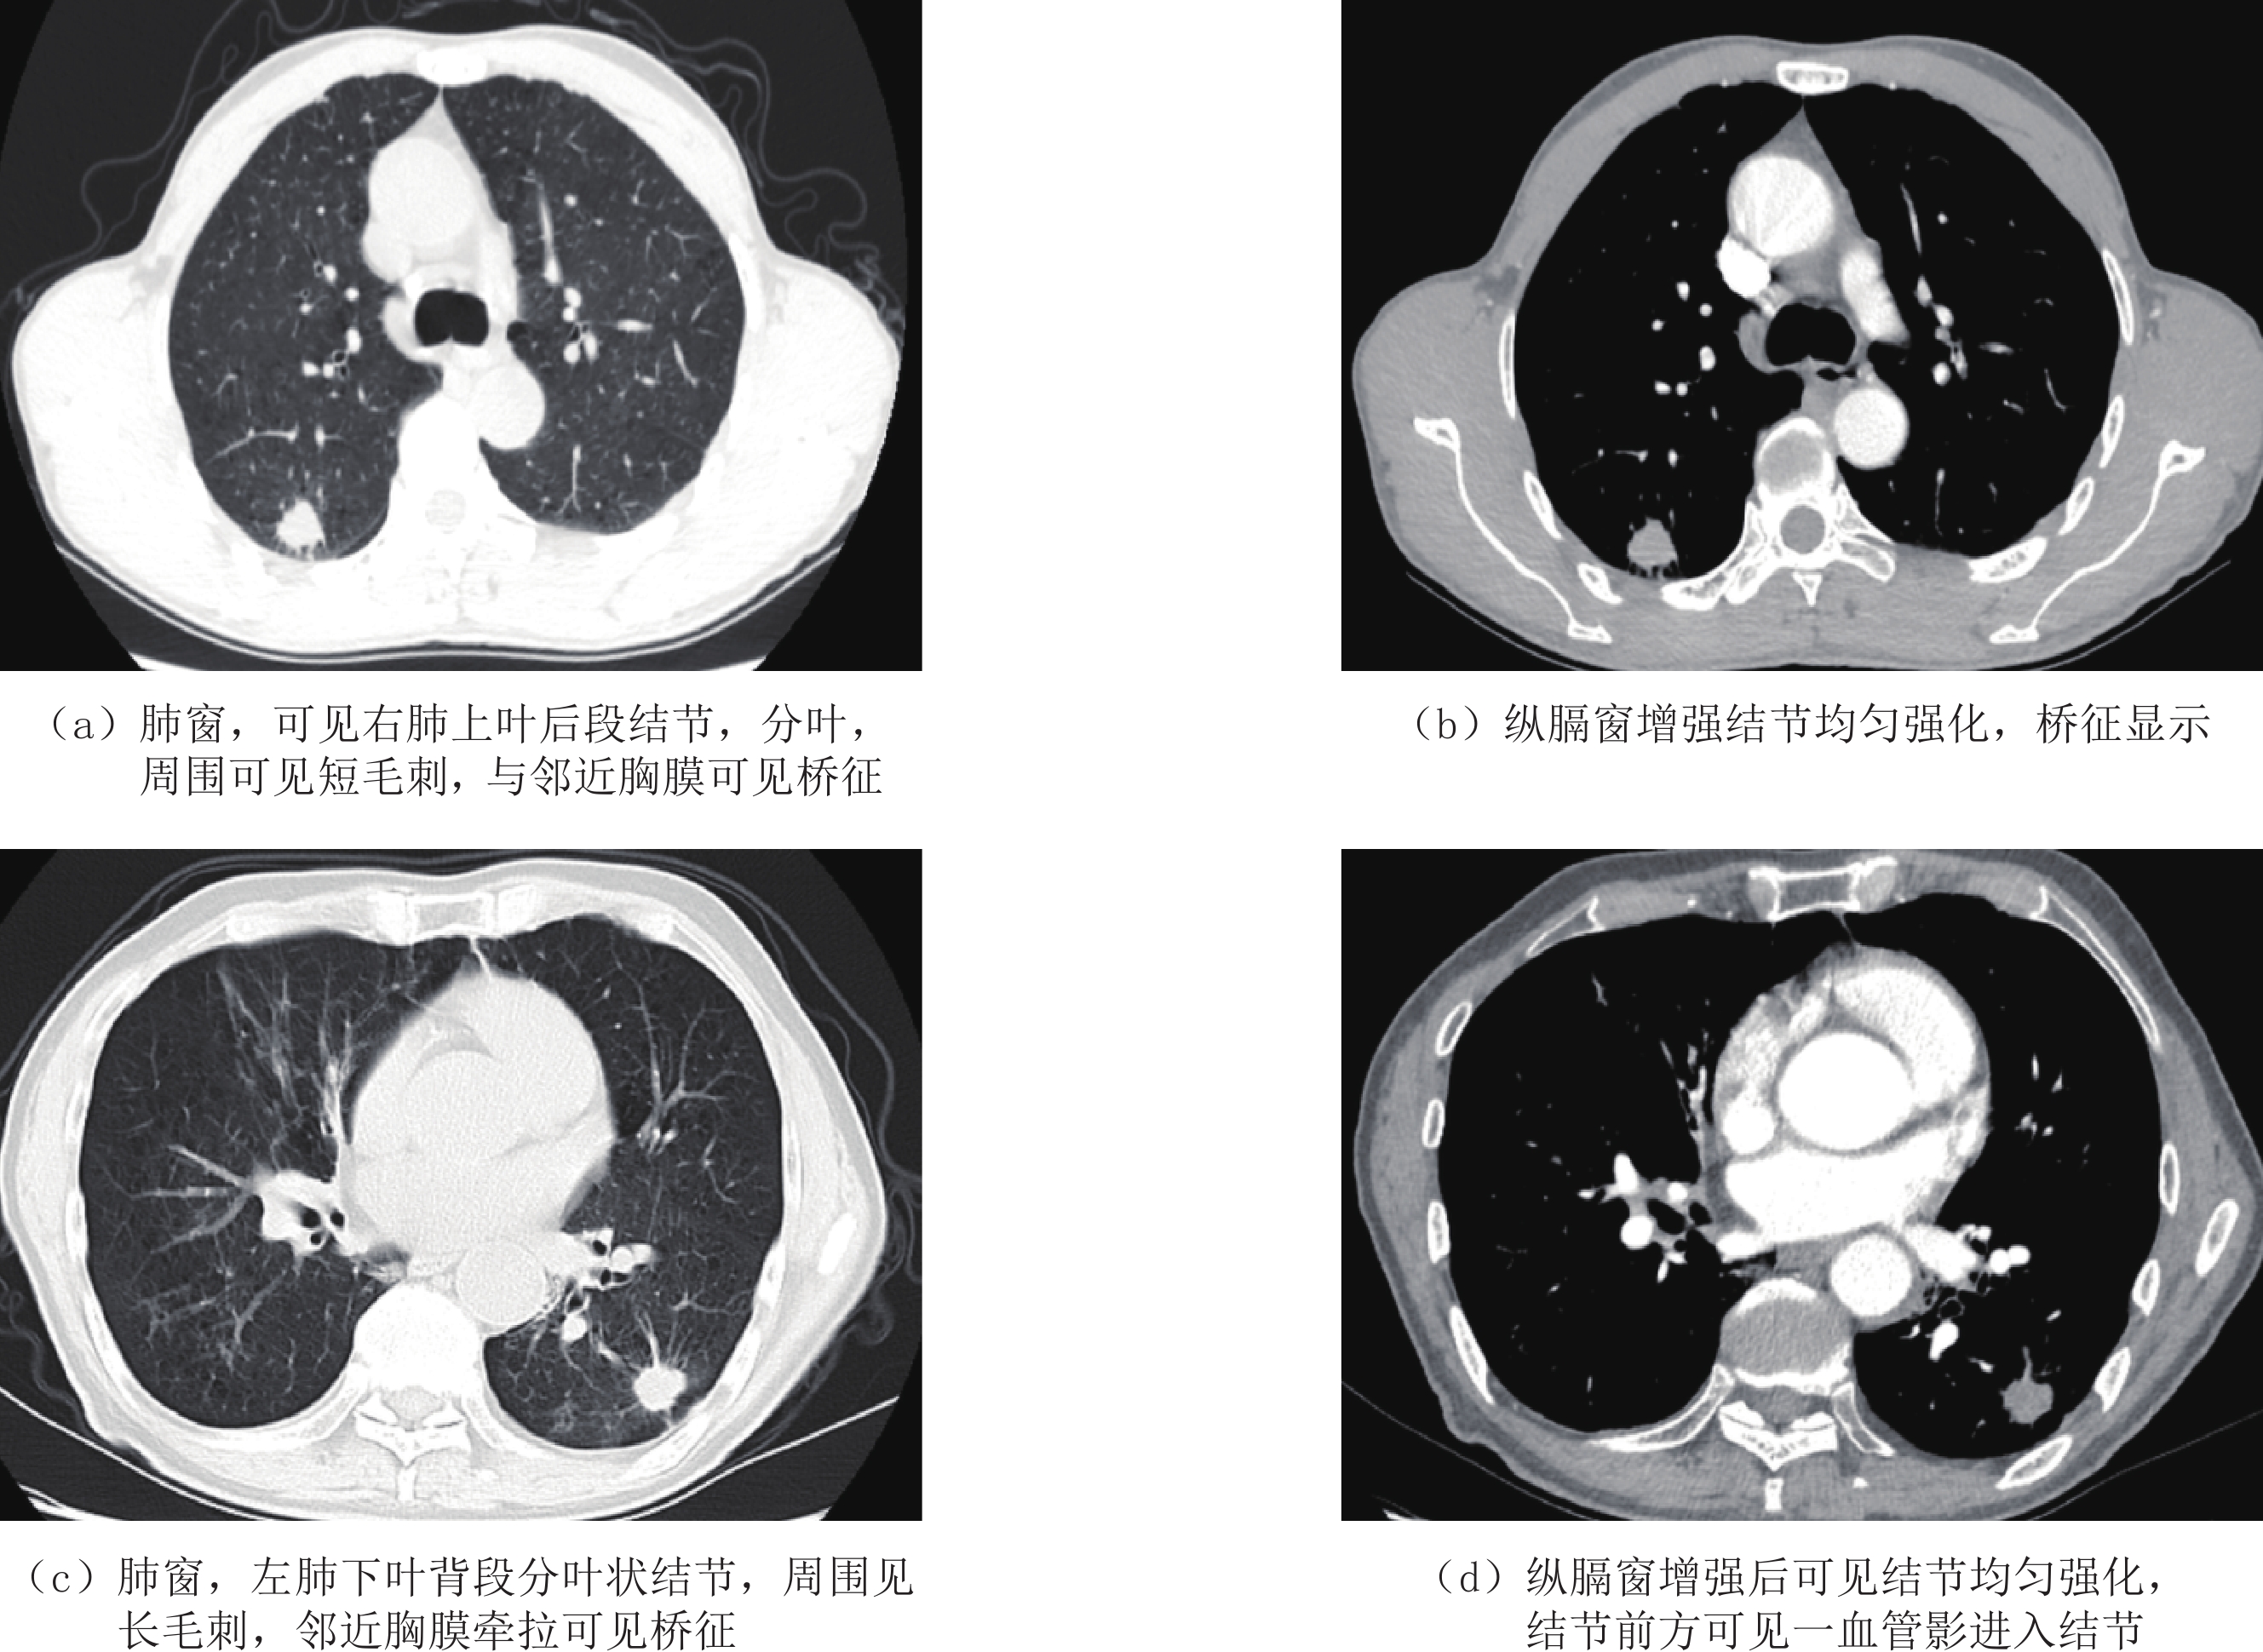

记录判断病灶与胸膜间桥征、支气管改变、血管集束征、病灶密度类型、病灶形状、边界是否模糊及内部结构情况。桥征判定标准为CT肺窗下观察到病灶与胸膜间拱形线样影,且边缘呈扁平化改变;血管集束征是指病灶周围血管向病灶方向汇集;支气管改变是指周围支气管病灶内扭曲走行,或僵硬或截断[7]。

以往有关CT影像学特征与肺癌脏层胸膜侵犯报道中绝大部分关注病灶本身,对于病灶形态学征象涉及较少[11]。本研究单因素和多因素分析结果显示,桥征与血管集束征均是早期胸膜下肺腺癌脏层胸膜侵犯发生独立危险因素。

有报道提示实性成分直径≤3 cm且合并脏器胸膜侵犯非小细胞肺癌患者89% 存在桥征,其形成可能与病灶与胸膜大范围接触及胸膜凹陷呈梯形改变有关[12];但本研究提示这一征象单一预测效能偏低,是否能够提高预测准确度仍需进一步探索验证。而血管集束征出现主要与病灶浸润生长至周围肺血管支气管束间,而病灶内纤维反应性增生对肺血管造成牵拉导致局部聚集造成,同时随病灶恶性程度增加牵拉效应亦更为明显,而这亦支持血管集束征与早期胸膜下肺腺癌脏层胸膜侵犯间的关系[13-14]。

3.2 胸膜毗邻关系与早期胸膜下肺腺癌脏层胸膜侵犯间的关系

已有研究显示,胸膜下肺癌但病灶与胸膜间未见影像学线样影关系,发生脏层胸膜侵犯风险极低[15]。本研究结果提示,胸膜毗邻关系分型中Ⅱ型及Ⅲ 型是早期胸膜下肺腺癌脏层胸膜侵犯独立危险因素。

有报道提示,肺癌病灶与胸膜关系中 Ⅲ型患者发生脏层胸膜侵犯风险最高[16],与本研究结果一致。我们认为胸膜毗邻关系与早期胸膜下肺腺癌脏层胸膜侵犯间的独立关系可能与以下因素有关。

早期病灶肿瘤细胞可能通过肿瘤与胸膜间线样影或条状影所建立通道向周围胸膜侵犯,但因病灶内纤维反应性增生相对轻微,并未引起邻近胸膜凹陷;而随病灶内纤维反应性增生及浸润程度加重,可导致周围胸膜牵拉凹陷且范围扩大,最终在CT扫描下呈Ⅱ型及 Ⅲ型改变[17-18]。